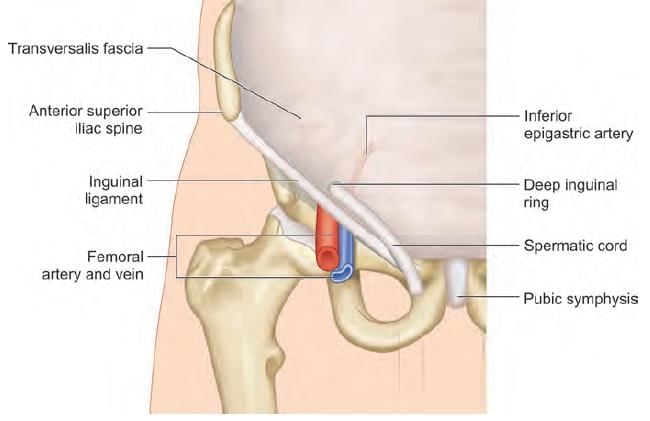

Hernia lying medial to inferior epigastric artery and superior to pubic tubercle, occurs due to weakness in: (NEET-PG 2023)

Superior boundary of the arrow marked structure is: (INI-CET July 2021)